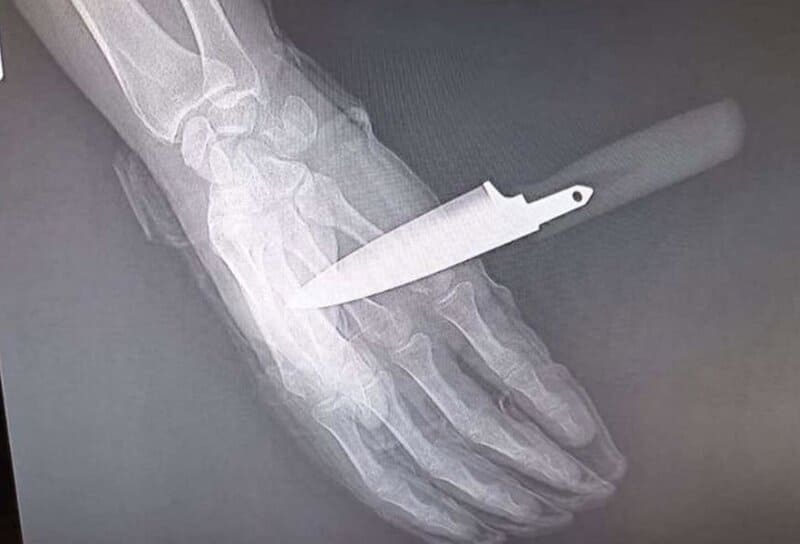

Radiografía de la mano del agente de la Policía Nacional apuñalado en Baza (Granada) - UNIÓN FEDERAL DE POLICÍA (UFP)

Acto seguido, el atacante intentó asestar una segunda puñalada que el policía logró repeler parcialmente, aunque el arma blanca llegó a atravesarle la mano.

No obstante, el agente hizo uso de su extensible reglamentaria y con la colaboración de su compañera consiguió reducir y detener al agresor, que fue trasladado a dependencias policiales para su ingreso en calabozos. Por su parte, el agente herido tuvo que acudir a un centro hospitalario con el cuchillo aún clavado.